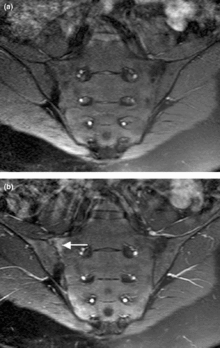

Magnetic resonance images of sacroiliac joints. Shown are T1-weighted semi-coronal magnetic resonance images through the sacroiliac joints (a) before and (b) after intravenous contrast injection. Enhancement is seen at the right sacroiliac joint (arrow, left side of image), indicating active sacroiliitis.